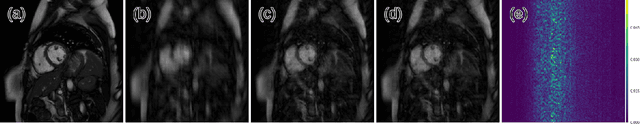

Abstract:Accelerating the data acquisition of dynamic magnetic resonance imaging (MRI) leads to a challenging ill-posed inverse problem, which has received great interest from both the signal processing and machine learning community over the last decades. The key ingredient to the problem is how to exploit the temporal correlation of the MR sequence to resolve the aliasing artefact. Traditionally, such observation led to a formulation of a non-convex optimisation problem, which were solved using iterative algorithms. Recently, however, deep learning based-approaches have gained significant popularity due to its ability to solve general inversion problems. In this work, we propose a unique, novel convolutional recurrent neural network (CRNN) architecture which reconstructs high quality cardiac MR images from highly undersampled k-space data by jointly exploiting the dependencies of the temporal sequences as well as the iterative nature of the traditional optimisation algorithms. In particular, the proposed architecture embeds the structure of the traditional iterative algorithms, efficiently modelling the recurrence of the iterative reconstruction stages by using recurrent hidden connections over such iterations. In addition, spatiotemporal dependencies are simultaneously learnt by exploiting bidirectional recurrent hidden connections across time sequences. The proposed algorithm is able to learn both the temporal dependency and the iterative reconstruction process effectively with only a very small number of parameters, while outperforming current MR reconstruction methods in terms of computational complexity, reconstruction accuracy and speed.

Abstract:Inspired by recent advances in deep learning, we propose a framework for reconstructing dynamic sequences of 2D cardiac magnetic resonance (MR) images from undersampled data using a deep cascade of convolutional neural networks (CNNs) to accelerate the data acquisition process. In particular, we address the case where data is acquired using aggressive Cartesian undersampling. Firstly, we show that when each 2D image frame is reconstructed independently, the proposed method outperforms state-of-the-art 2D compressed sensing approaches such as dictionary learning-based MR image reconstruction, in terms of reconstruction error and reconstruction speed. Secondly, when reconstructing the frames of the sequences jointly, we demonstrate that CNNs can learn spatio-temporal correlations efficiently by combining convolution and data sharing approaches. We show that the proposed method consistently outperforms state-of-the-art methods and is capable of preserving anatomical structure more faithfully up to 11-fold undersampling. Moreover, reconstruction is very fast: each complete dynamic sequence can be reconstructed in less than 10s and, for the 2D case, each image frame can be reconstructed in 23ms, enabling real-time applications.